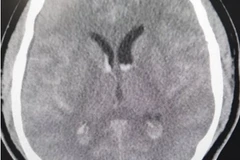

Chảy máu dưới nhện lan tỏa là một tổn thương có vị trí khó, phức tạp và tinh vi, cần một bác sỹ chẩn đoán hình ảnh chuyên sâu và nhiều kinh nghiệm mới chẩn đoán được.

Theo bác sỹ Trần Quang Lục, Trưởng khoa Chẩn đoán hình ảnh thực hiện chụp CT cùng phần mềm RAPID, từ 18/6 vừa qua, hơn 60 ca bệnh tại Bệnh viện đa khoa Phú Thọ được ứng dụng trí tuệ nhân tạo RAPID.